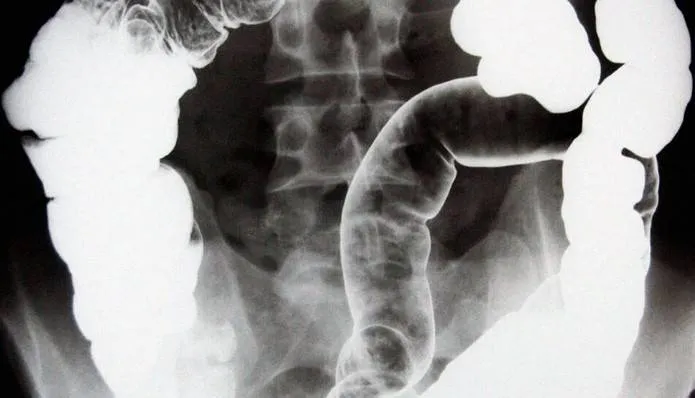

يتطلب تشخيص مرض التهاب الأمعاء (IBD) اتباع نهج متعدد الخطوات، وفقًا للدكتور دوبل الذي يشرح: سيناقش الأطباء أولًا تاريخك الطبي وأعراضك، يليه فحص جسدي للتحقق من الالتهاب أو الألم. وقد يوصى بإجراء اختبارات مختلفة، بما في ذلك تنظير القولون أو التنظير السيني للحصول على رؤية مباشرة داخل القولون، وتقنيات التصوير مثل الأشعة المقطعية أو التصوير بالرنين المغناطيسي لرؤية الجهاز الهضمي بالكامل، واختبارات الدم للتحقق من علامات الالتهاب وفقر الدم وعوامل أخرى.